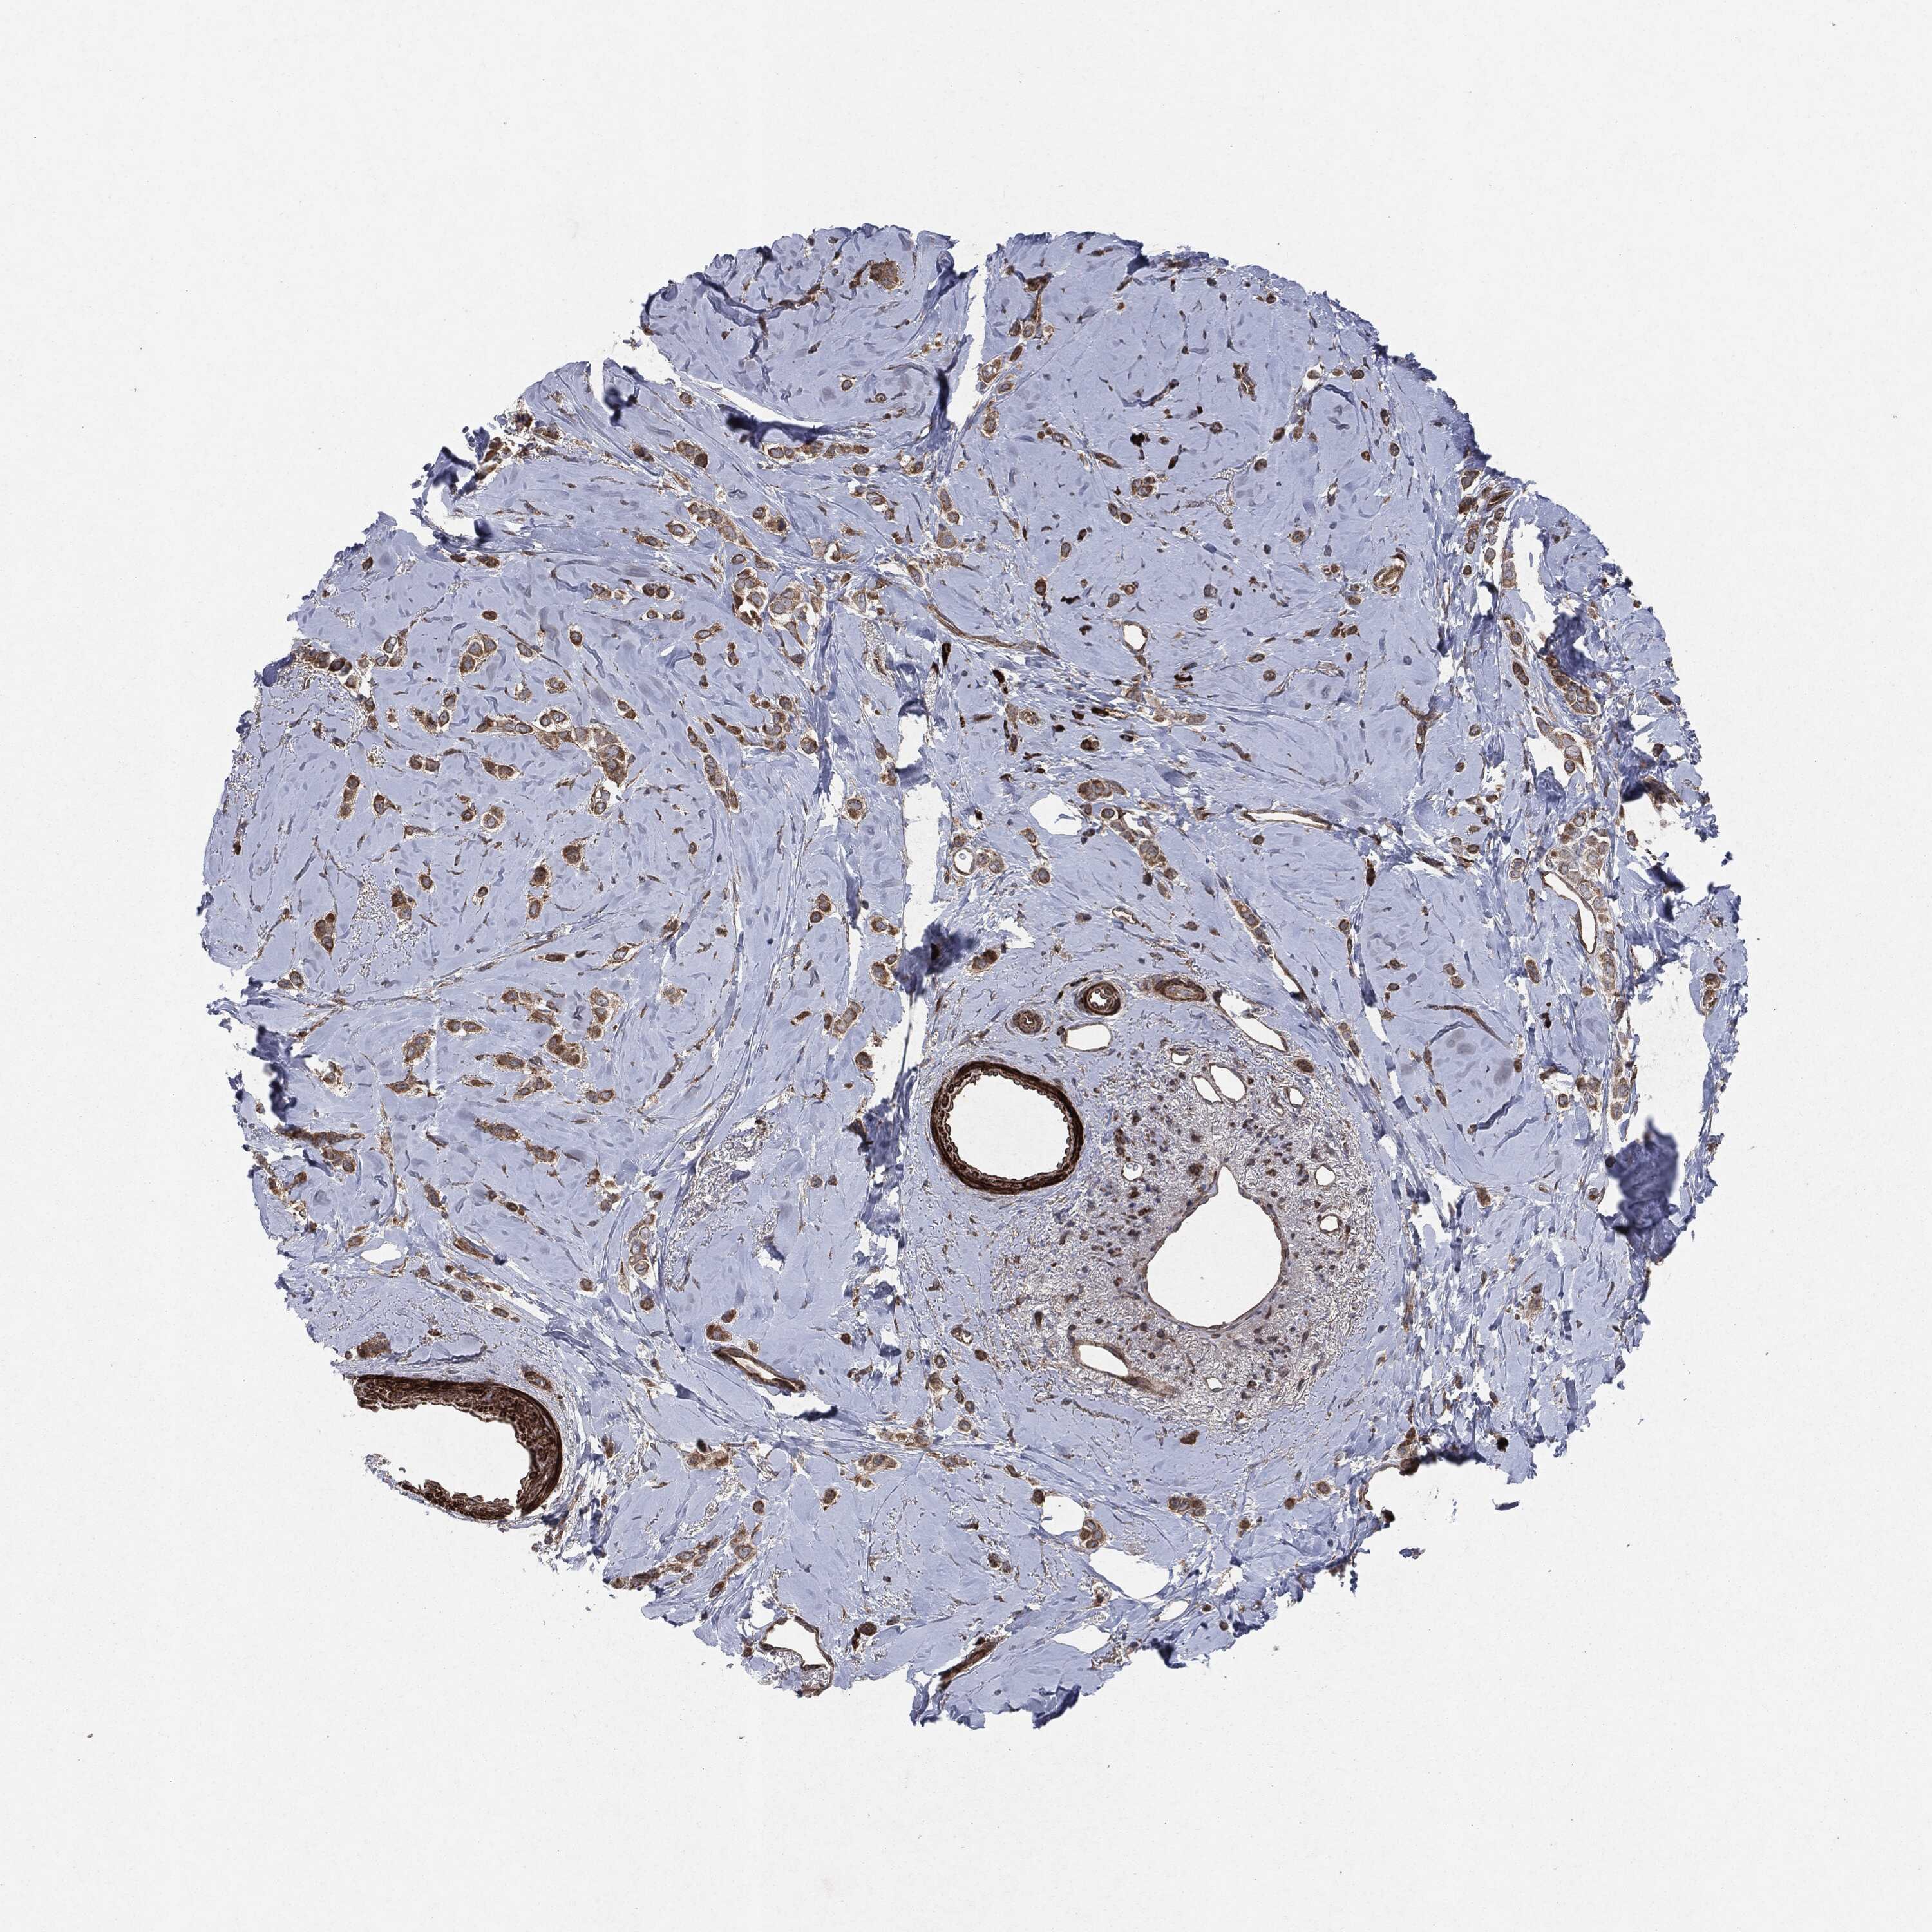

BRCA TCGA BRCA VALIDATION PROTEIN EXPRESSION